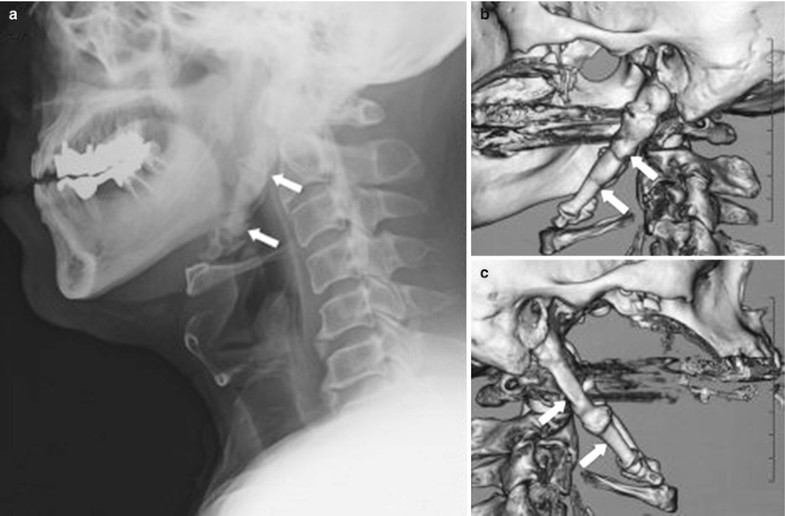

From radiologykey.com

Glossopharyngeal Nerve Block Radiology Key Glossopharyngeal Nerve Block For Pain Relief Twelve patients completed a total of 48 injections for glossopharyngeal nerve block. The glossopharyngeal nerve block (gpnb) is used primarily in pain management in cases of neuralgia as well as to abolish the gag reflex for. The mean procedure time was 9.51±0.89 mins. A regional anesthetic technique formerly used in adults for tonsillectomy was adapted to provide posttonsillectomy pain relief. Glossopharyngeal Nerve Block For Pain Relief.

Glossopharyngeal Nerve Block Radiology Key Glossopharyngeal Nerve Block For Pain Relief This study aimed to assess. A regional anesthetic technique formerly used in adults for tonsillectomy was adapted to provide posttonsillectomy pain relief in. Twelve patients completed a total of 48 injections for glossopharyngeal nerve block. A modification of this technique, termed glossopharyngeal nerve block (gnb), which uses bupivacaine, was introduced at our institution. The glossopharyngeal nerve block (gpnb) is used. Glossopharyngeal Nerve Block For Pain Relief.